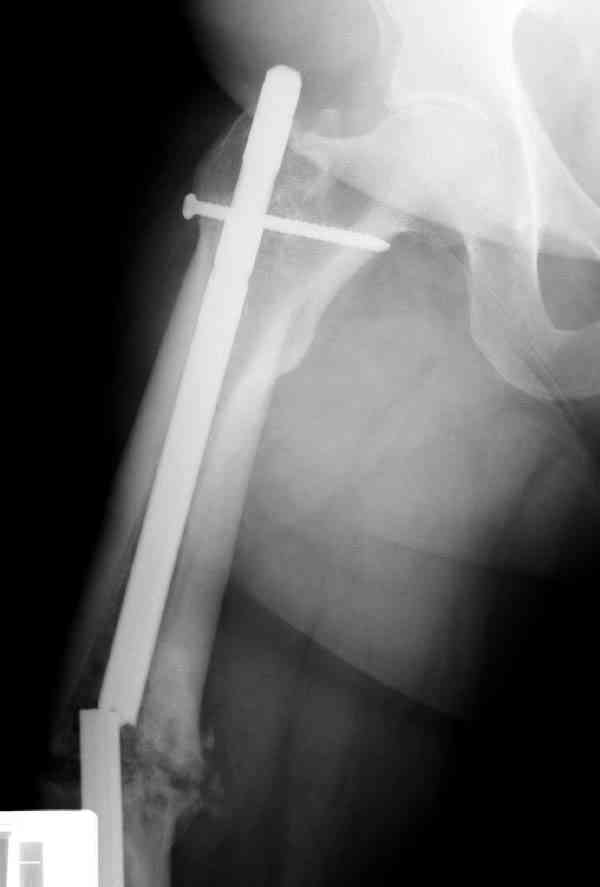

Сросшаяся малоберцовая как распорка привела к образованию ложного

сустава. В таких случаях удаляем сломанный штифт и проводим

стимуляцию ложного сустава рассверливанием. Рассверливание канала

создает стимуляцию на месте ложного сустава, и динамический вариант

блокировки штифта с большим диаметром создаст стабильность. Ранняя

нагрузка после остеотомии малоберцовой приведет к сращению ложного

сустава.